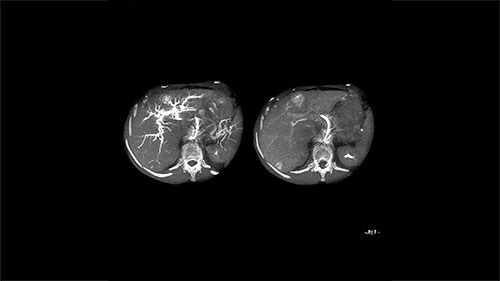

Step 1 – See

XperCT Dual allows two phases of a contrast injection to be displayed next to each other. Clinicians can assess the feeder vessels to a tumor in the arterial phase and see the tumor boundaries in the delayed phase. Studies have shown that this novel method is superior to conventional DSA and provides equivalent imaging information to the gold standard of contrast enhanced MRI.³ ⁶

EmboGuide is based on XperCT Dual, a dedicated type of 3D oncologic imaging, which is used to visualize tumors and their feeding vessels.

Arterial phase

Delayed phase